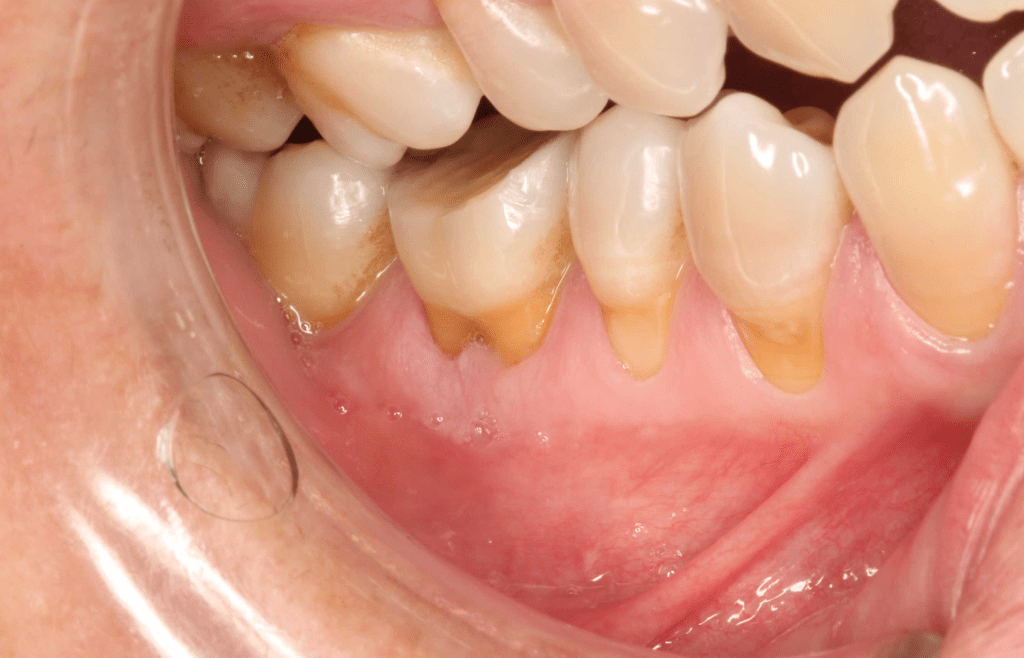

Reco pared vesticular